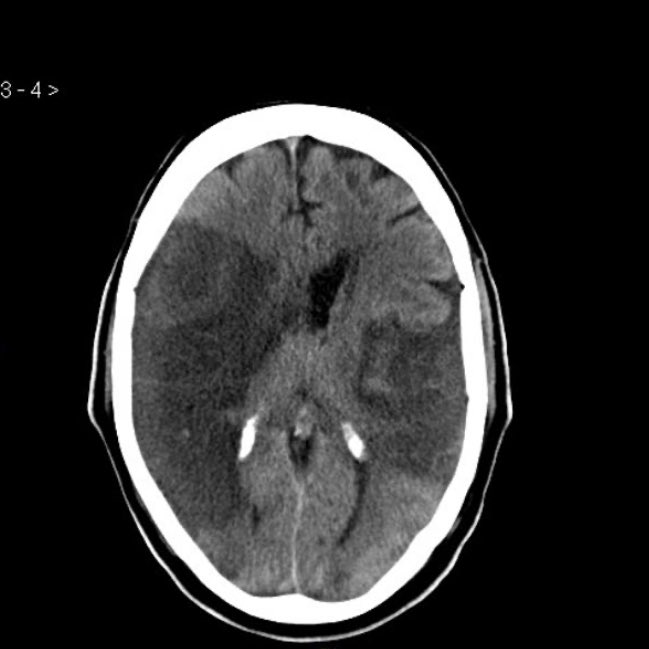

▫️intracerebral hemorrhage🩸🧠

✳️Blood in the parenchyma that is well defined